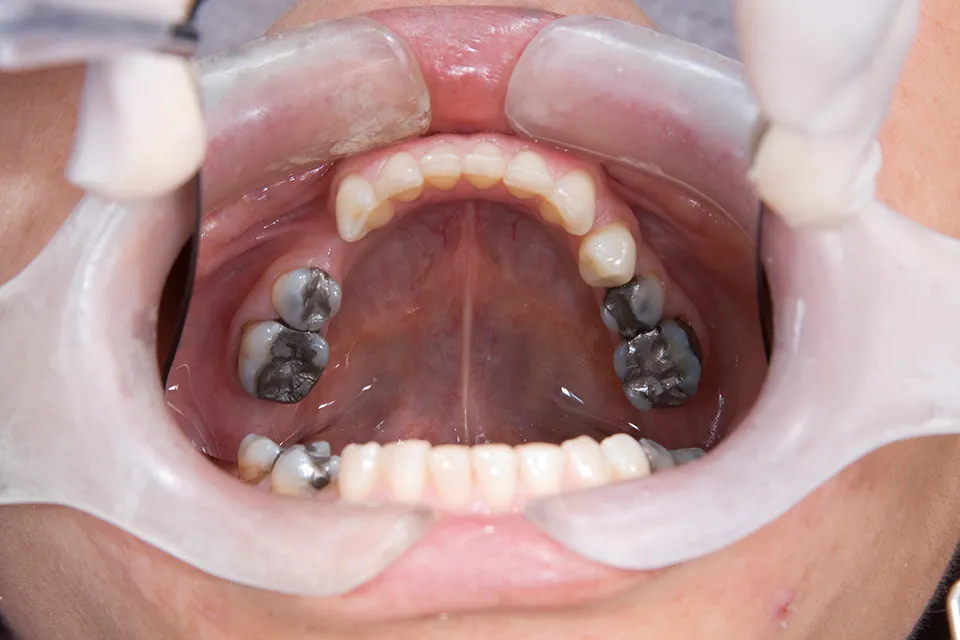

6 Types of Dental Fillings

Dental fillings play an essential role in maintaining good oral health. If you have a cavity or a damaged tooth, a filling can help restore its strength and function. Furthermore, Dental Land in Summerhill, Ontario, provides various types of dental fillings to meet your needs. This guide will examine the various types of dental fillings […]